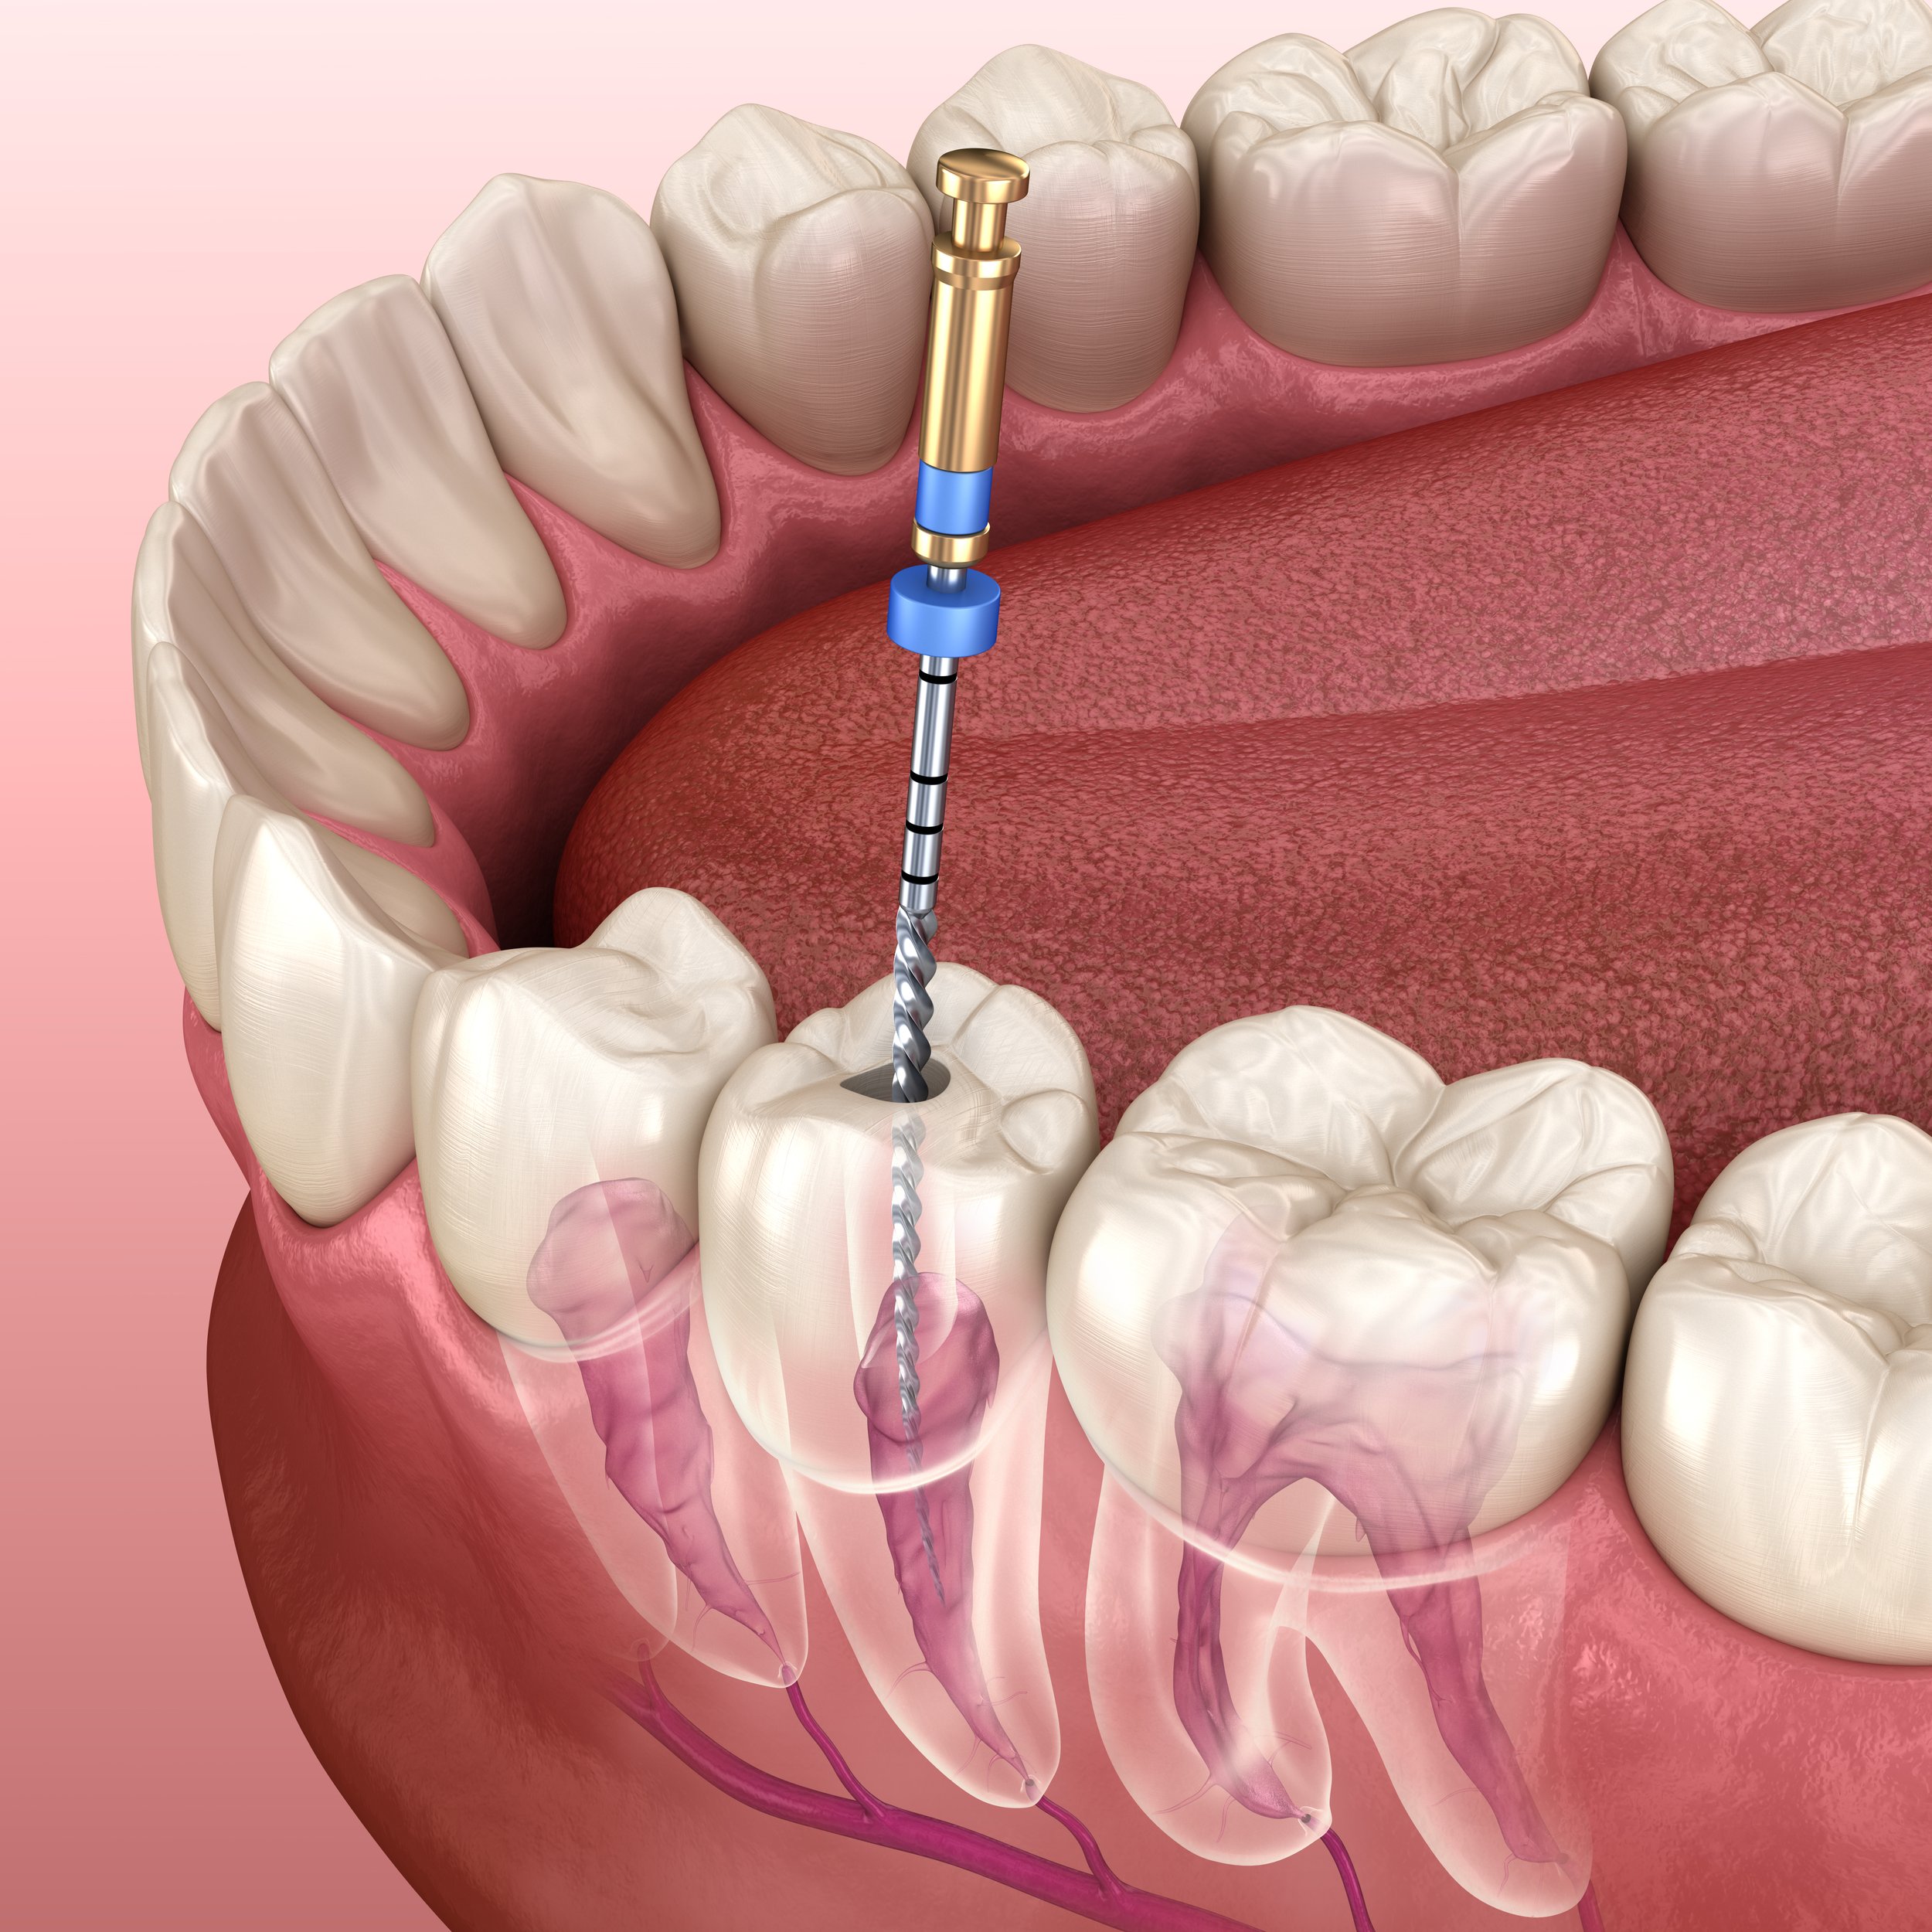

I had a very good experience with my emergency root canal here, this clinic is very accommodating to all last minute dental needs. Ankur is very thorough and thoughtful, he can help you soothe out of pain immediately as he did with me. My RCT was painless and quick. The prices here are very fair I would definitely recommend this to family and friends!

Dr Ankur is very experienced hand, had an infected RCT case, Thanks to him for taking my case as an emergency! Skillful hands!